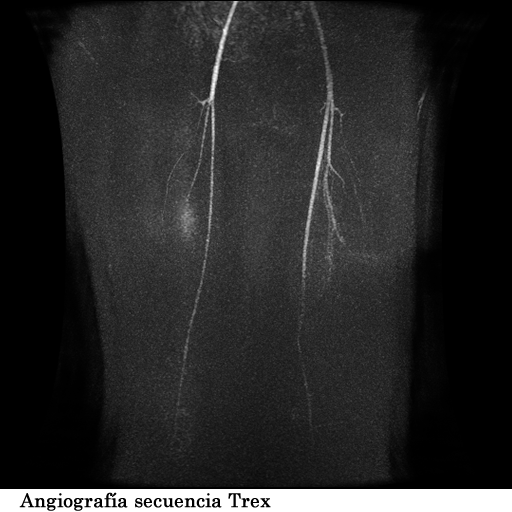

Se coloco al paciente en decúbito supino, utilizando una bobina fase array, haciendo adquisiciones en los planos axial, sagital y coronal, secuencias, spin echo, eco de gradiente e hibridas, potenciadas a T1, T2 y DP, secuencias Steer, y se obtuvieron imágenes con saturación de grasa.

1. Edema de tejidos blandos que infiltra los músculos del muslo en su tercio medio y distal

2. Fractura patológica de tercio proximal de la diáfisis femoral izquierda

3. Engrosamiento del periostio del tercio medio y distal de la diáfisis femoral izquierda